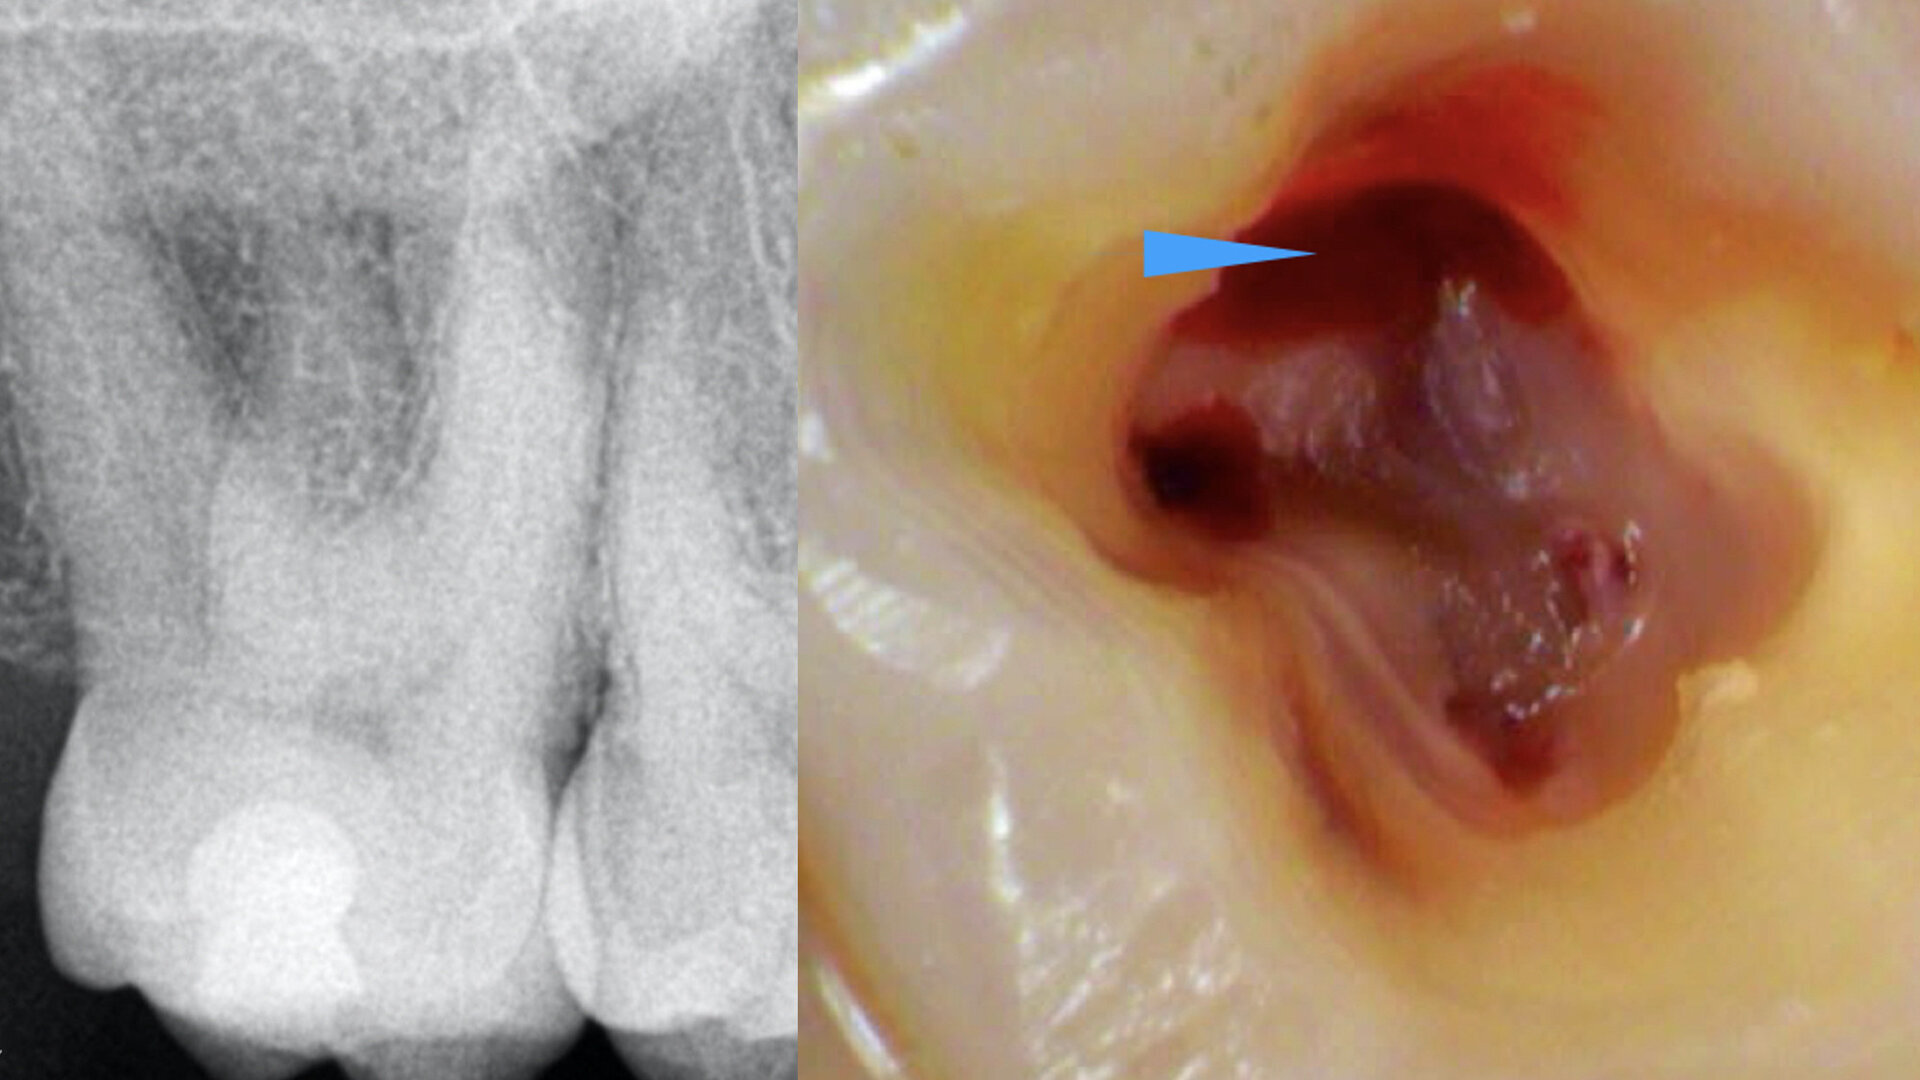

This type of anatomy is the most challenging, as it requires all your skills and high-tech equipment. The patient was referred for irreversible pulpitis of a maxillary second molar. Upon examining the preoperative radiograph (Fig. 12), we could see that the anatomy was not clear. When creating the access cavity (Fig. 13), I saw only a small opening in the centre of the buccal area of the access cavity. Using ultrasonic instruments, very carefully and gently, I extended the access cavity more to the distal side and a bit deeper, preceding very slowly. It was like creating a second access cavity inside the first one. I had to go down almost 5 mm in order to uncover the opening of the distal canal, and the mesial canal and the isthmus between the two canals can be observed in Figure 14.

The immediate postoperative radiograph (Fig. 15) shows how deep the furcation and the isthmus between the two canals were. This kind of anatomy is very difficult to establish and treat in teeth to which access is relatively easy. We could unfortunately not find a micro-CT reconstruction of such an anatomy, as performing a root canal therapy on a maxillary second molar is not common, being rather difficult. We can easily miss a canal and thereby the whole treatment is jeopardised.